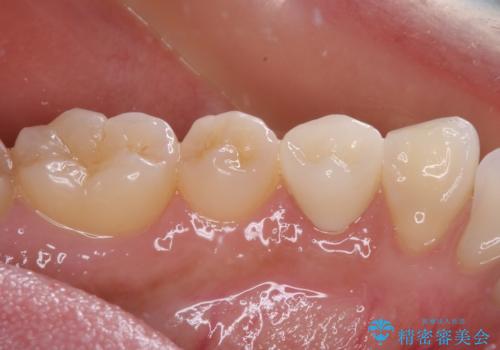

痛みでうずく 根管治療と補綴治療

- 下顎の小臼歯が食事などの度に痛みを感じるとのことで来院された患者様です。

レントゲン写真などで診査を行ったところ、左下の第一小臼歯の神経組織が壊死し、根尖部周辺の骨に炎症が認められました。

まずは根管治療を行い、症状が消退したことを確認してオールセラミッククラウンにて補綴治療を行うこととしました。

根管治療後6ヶ月でレントゲン写真を撮影したところ、根尖部周辺の炎症が消退していることが認められました。